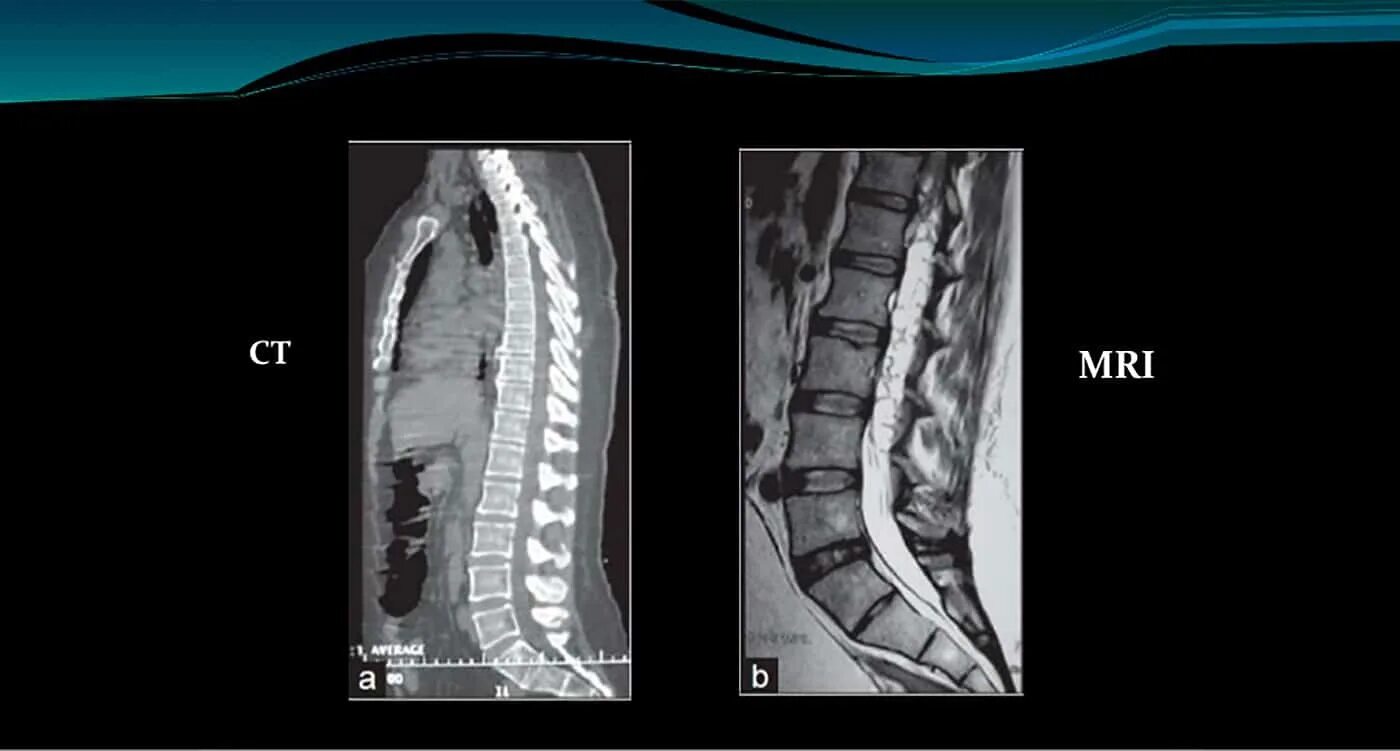

Чем отличается кт от мрт поясничного отдела